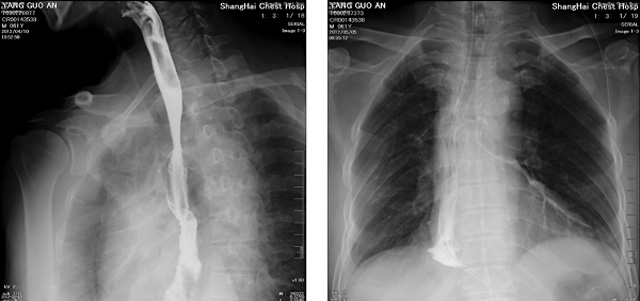

DR設(shè)備在2020年的新冠疫情中,加速了市場調(diào)整。以醫(yī)院為主的向二三級市場轉(zhuǎn)變。特別是小巧靈活的移動DR設(shè)計,填補CT和磁共振不能三維檢查的缺點,滿足內(nèi)科外科特別是骨科的影像診斷需求。還有懸吊DR設(shè)備CT斷層射線系統(tǒng)。使用錐束成像技術(shù)對整個脊柱和整個下肢進行了體積三維掃描。無需使用對比劑,即可使用X射線呼吸功能標測來模擬模擬氣流和血流,以評估患者的肺動脈血栓。

數(shù)字化X線攝影依然是患者初篩的關(guān)鍵一環(huán)。靜態(tài)DR限制于探測器平臺。只能進行簡單普通的數(shù)字化影像檢查。胸部的疾病沒辦法篩查出微小的病灶。這樣導(dǎo)致DR慢慢的被CT跟磁共振代替。這樣造成了原來配套的數(shù)字化影像DR設(shè)備的 閑置。所以DR需要跟CT融合擴大DR的檢查使用場景。為DR提高更多的市場價值。X射線技術(shù)的原始形式和面向未來的可能性打破了CT成像和DR成像掃描技術(shù)之間的限制。融合成像趨勢更加明顯,多峰成像趨勢發(fā)展更加迅速。